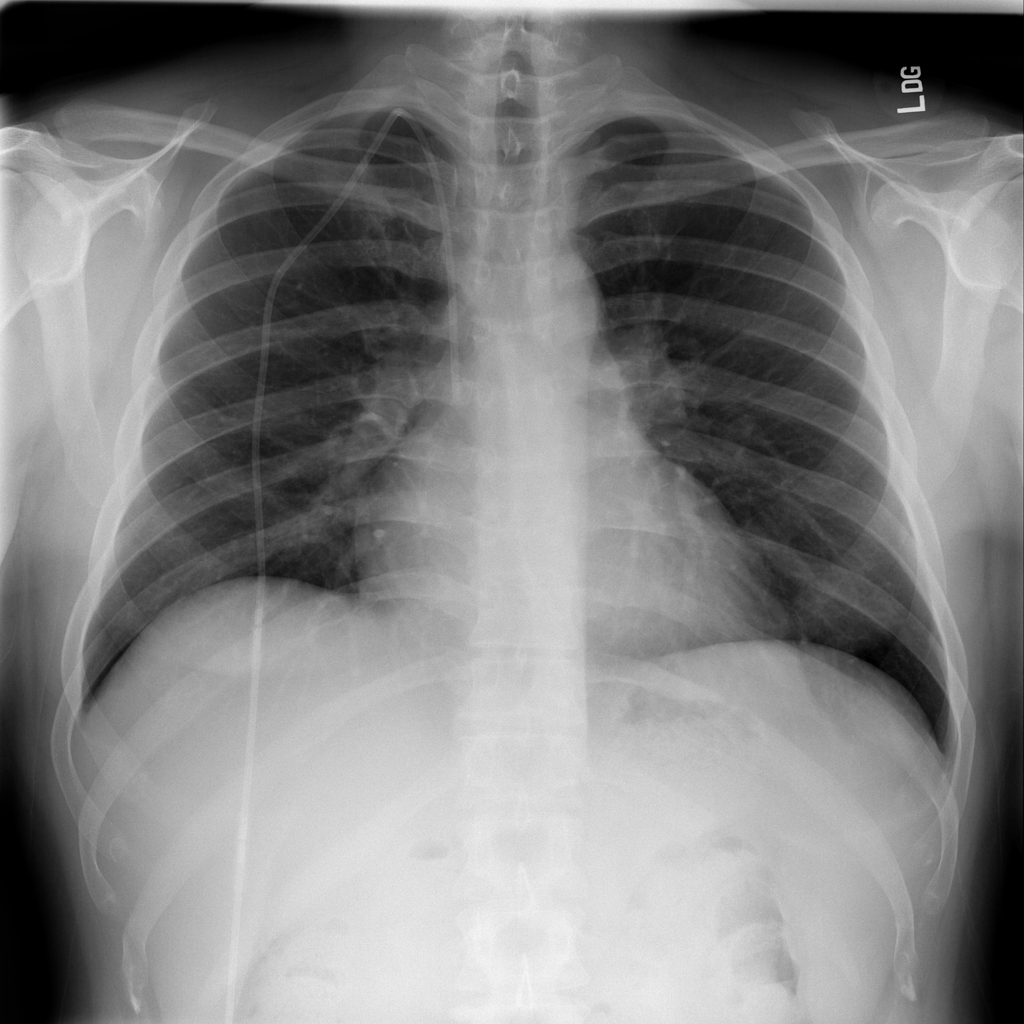

COPD / Emphysema

COPD and emphysema are chronic lung diseases that can change chest X-ray appearance but are not diagnosed by X-ray alone.